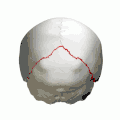

Animation. Lambdoid suture shown in red. -